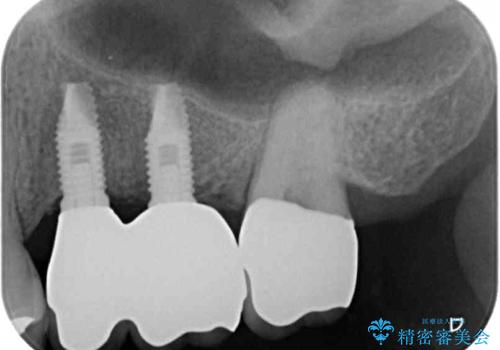

ブリッジの支台を抜歯したことで2本のインプラントが必要であり、その後方はインプラント埋入に必要な骨量が不足していたため、上顎洞粘膜の挙上を行うこととしました。

また、残っている最後方歯は手前に倒れてきていたため、部分矯正により奥に移動させてから、インプラント埋入を行うこととしました。

部分矯正期間中はアンカースクリューやフック、ゴムなどが粘膜にあたり、大変な思いをすることになりましたが、そのおかげでインプラント補綴した歯と最後方歯の位置が非常に良好となり、まるでご自身の歯のように咬むことができるようになりました。